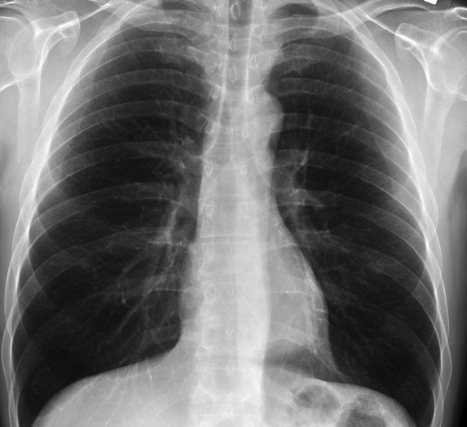

Location of the Heart on an X-Ray

Figure 8.2: Location of the Heart on an X-Ray

The heart is between the lungs and slightly oriented to the left (in most individuals) - it is also a part of the body’s circulatory system (obviously)!